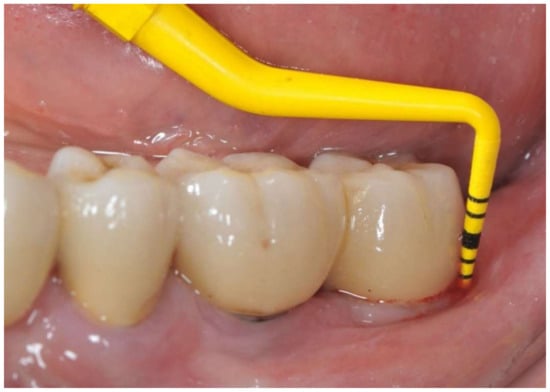

A 65-year-old woman with a noncontributory medical history was referred to the Oral Surgery Unit, Policlinico Umberto I, “Sapienza” University of Rome, Italy, to undergo surgical reconstructive therapy peri-implantitis lesion localized around the mandibular left distal implant (Figure 1 and Figure 2). The patient’s written detailed informed consent was obtained for the diagnostic and therapeutic approach and the use of the documentation for research purposes and publishing.

Figure 1. Buccal view before peri-implant therapy: bleeding on probing and probing depth of 7 mm around the distal implant.